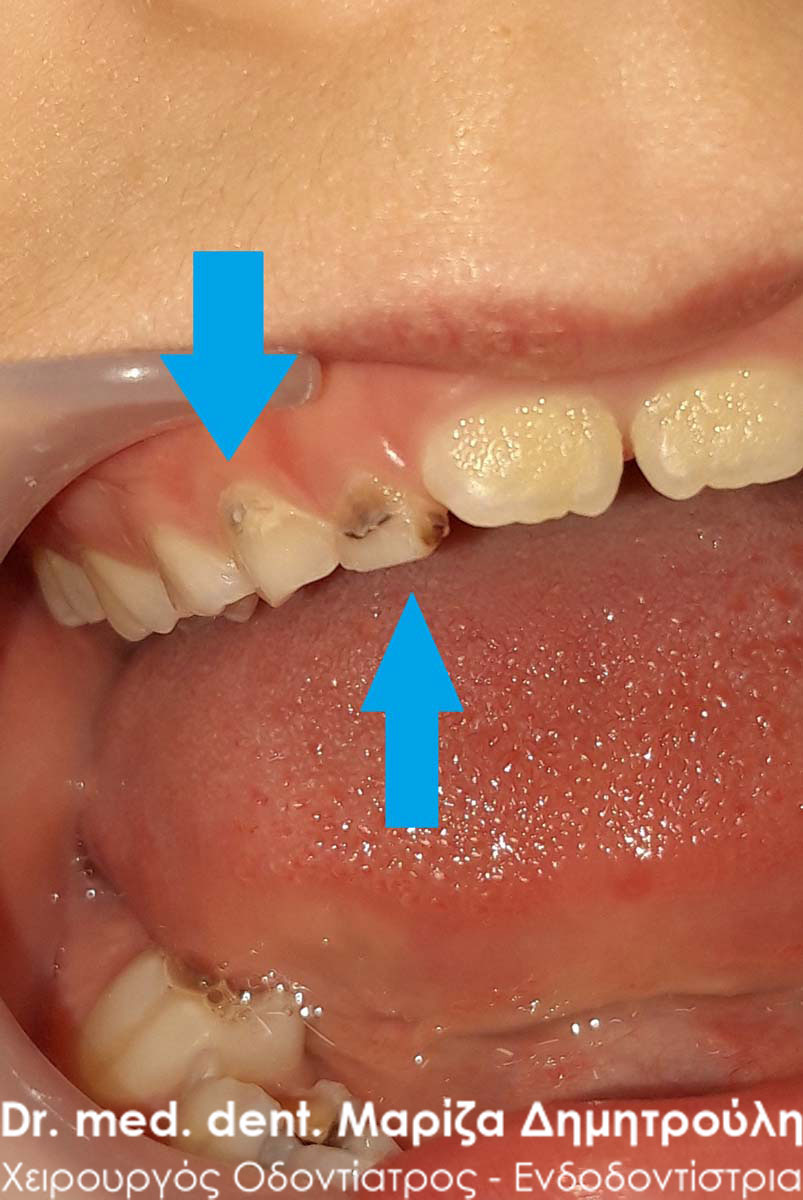

Επίσης στην πρόσθια περιοχή της άνω γνάθου παρατηρήθηκε ένα μικρό συρίγγιο στην περιοχή του πρώτου αριστερού νεογιλού γομφίου, ο οποίος είχε έντονη κινητικότητα χωρίς όμως να “πέφτει”. Στην περίπτωση αυτή ήταν απαραίτητη η εξαγωγή του νεογιλού δοντιού, γιατί το παιδί είχε το συρίγγιο τουλάχιστον τις τελευταίες 3 εβδομάδες (σύμφωνα πάντα με τα λεγόμενα της μητέρας). Με την εξαγωγή του δοντιού το συρίγγιο υποχώρησε τις επόμενες μέρες και το παιδί ανακουφίστηκε.

Συρίγγιο στην περιοχή του πρώτου νεογιλού τομέα